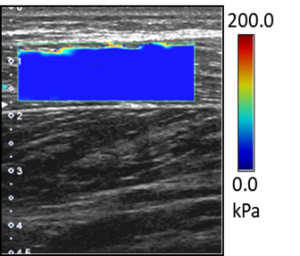

③ 最先端の技術であるせん断波エラストグラフィー機能で筋の硬さを評価した点

本研究で使用した超音波画像診断装置の画像の一つです.この機能で筋に伝わるせん断波の速度から筋の硬さである弾性率を算出し,その弾性率を指標としてフォームローリング効果を検討しました.その結果,5週間のフォームローリング介入によって筋の硬さには変化が生じなかった事が分かりました.